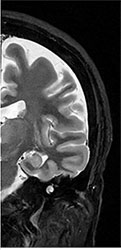

![]() CT画像 |

脳梗塞、脳腫瘍、脳出血、その他の変性疾患を診断することができます。また、造影剤を用いること無く、血管を明瞭に描出し、動脈の瘤や狭窄を診断することができます。